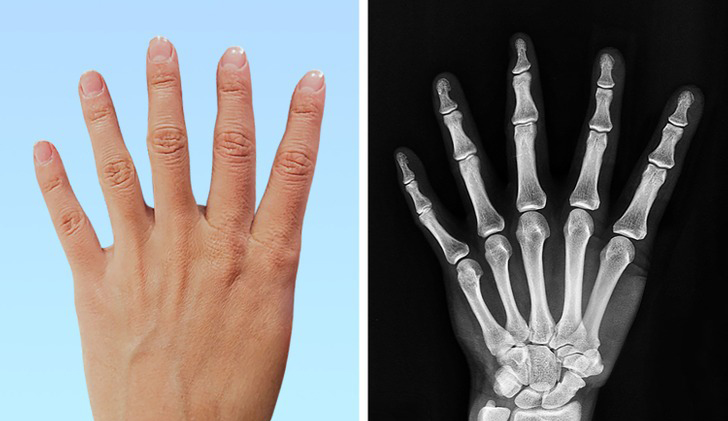

۱. داشتن انگشت شست با ۳ فالانژ (استخوان موجود در انگشتان) یا داشتن ۶ انگشت

به طور معمول انگشست شست دارای ۲ فالانژ یا استخوان و دستها دارای ۵ انگشست هستند. از این رو، تولد با شست با ۳ فالانژ یا داشتن انگشت ششم مطمئناً یک موضوع غیرعادی و نادر به نظر میرسد. از هر ۱۰۰۰ نفر فقط ۱ نفر انگشت ششم دارد و از هر ۲۵۰۰۰ نفر ۱ نفر دارای انگشت شست ۳ فالانژه میباشد. با این حال، این یک معلولیت غیرعادی و آسیب رسان نیست و حتی در برخی زمینهها مزایای زیادی نیز به همراه دارد. پزشکان بر این باورند که مغز این افراد کاملاً قادر به کنترل اندام اضافی است و مغز هیچ تمایزی بین اندام اضافی با سایر قسمتهای بدن قائل نمیشود.